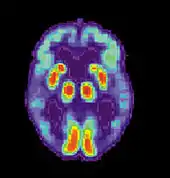

Alzheimer's disease is characterised by loss of neurons and synapses in the cerebral cortex and certain subcortical regions. This loss results in gross atrophy of the affected regions, including degeneration in the temporal lobe and parietal lobe, and parts of the frontal cortex and cingulate gyrus.[93] Degeneration is also present in brainstem nuclei like the locus coeruleus.[94] Studies using MRI and PET have documented reductions in the size of specific brain regions in people with AD as they progressed from mild cognitive impairment to Alzheimer's disease, and in comparison with similar images from healthy older adults.[95][96]

Alzheimer's disease is usually diagnosed based on the person's medical history, history from relatives, and behavioural observations. The presence of characteristic neurological and neuropsychological features and the absence of alternative conditions is supportive.[116][117] Advanced medical imaging with computed tomography (CT) or magnetic resonance imaging (MRI), and with single-photon emission computed tomography (SPECT) or positron emission tomography (PET) can be used to help exclude other cerebral pathology or subtypes of dementia.[118] Moreover, it may predict conversion from prodromal stages (mild cognitive impairment) to Alzheimer's disease.[119]

Due to low accuracy, the C-PIB-PET scan is not recommended to be used as an early diagnostic tool or for predicting the development of Alzheimer's disease when people show signs of mild cognitive impairment (MCI).[134] The use of ¹⁸F-FDG PET scans, as a single test, to identify people who may develop Alzheimer's disease is also not supported by evidence.[135]

Imaging

Of the many medical imaging techniques available, single photon emission computed tomography (SPECT) appears to be superior in differentiating Alzheimer's disease from other types of dementia, and this has been shown to give a greater level of accuracy compared with mental testing and medical history analysis.[295] Advances have led to the proposal of new diagnostic criteria.[22][121]

PiB PET remains investigational, but a similar PET scanning radiopharmaceutical called florbetapir, containing the longer-lasting radionuclide fluorine-18, is a diagnostic tool in Alzheimer's disease.[296][297]

Amyloid imaging is likely to be used in conjunction with other markers rather than as an alternative.[298] Volumetric MRI can detect changes in the size of brain regions. Measuring those regions that atrophy during the progress of Alzheimer's disease is showing promise as a diagnostic indicator. It may prove less expensive than other imaging methods currently under study.[299]

In 2011, an FDA panel voted unanimously to recommend approval of florbetapir.[300] The imaging agent can help to detect Alzheimer's brain plaques.[301] A negative scan indicates sparse or no plaques, which is not consistent with a diagnosis of AD.[302]